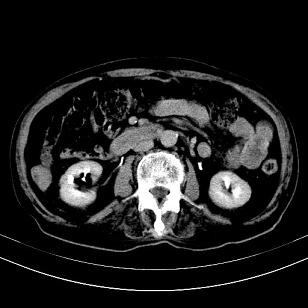

标题: CT19407:肝内还是肝外原发性肿瘤??

男,63岁,高血压病史40余年,

来源-右侧肾上腺。

考虑右侧肾上腺巨大占位;恶性?

另:右肾结识,多发小囊肿。

考虑右侧肾上腺肿瘤并肝内多发转移。右侧肾上腺呈“八”字形,包括内侧枝及外侧枝,内侧枝受压,考虑外侧枝原发肿瘤。”

考虑肝右后叶肝癌(部分外生)伴肝内多发性转移;不排除右侧肾上腺区恶性嗜铬细胞瘤并肝转移。